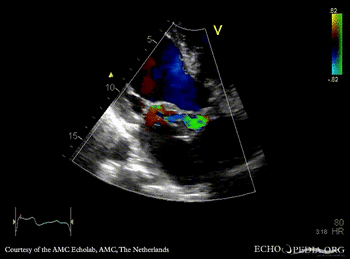

E00848.gif

A3CH